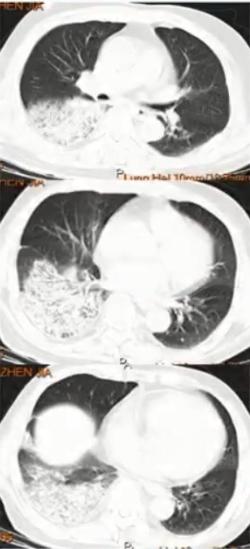

图3 双肺弥漫性小结节为主,中下肺布满粟粒样小结节,部分融合成片状

病例3

男,37岁,既往身体健康。因发热、咳嗽、咳黄痰1周入院。

日最高体温38.8℃-39.5℃,伴咽痛、肌痛、全身乏力,急诊血常规

WBC:8.74×109/L,N:0.865,予退热胶囊、头孢曲松、阿奇霉素等药物治疗3天无效。

CRP 12.10 mg/dl、PCT 0.107 ng/ml。

血清肺炎支原体抗体、肺炎衣原体抗体、军团菌抗体、流感病毒IgM均阴性。RT-PCR肺炎支原体核酸阳性。使用莫西沙星治疗14天后出院。

病原学诊断和转归

1. 病原学诊断

(1)入院次日BALF肺炎支原体核酸阳性

(2)血清肺炎支原体抗体,入院前为小于1:40;入院第14天为1:1280。

2. 转归

莫西沙星单药治疗2周后肺部阴影明显吸收

3. 诊断治疗面临的困难

• 临床表现不典型:咳黄痰

• 特殊的影像表现:中下肺弥漫小结节影

• 早期病原学检测无阳性发现

• 常规经验性治疗无效